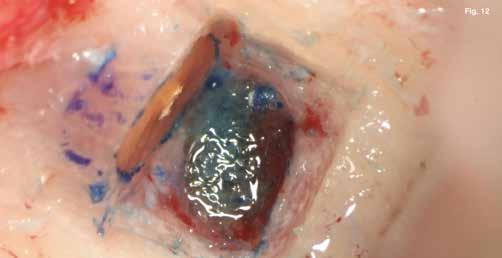

A szubmarginális teljes vastagságú lebenyt két felszabadító bemetszéssel végeztük egy 69-es számú, dupla lekerekített mikropengével (Swann–Morton) (6–7. ábra) A vestibularis csont ép volt, ezért csontablak-technikát alkalmaztunk és végeztünk (6–8. ábra) piezo készülékkel (Woodpecker DTE AI Surgery) és „US1, UC1” (Guilin Woodpecker Medical Instrument Co., LTD) hegyekkel. A blokkot az intraoperatív szakaszok alatt sóoldatban tartot-

tuk. Az apikális reszekciót (8. ábra) az „UC1” (Guilin Woodpecker Medical Instrument Co., LTD) segítségével végeztük el, és a gyökeret egy 3 mm-es „MM4” (Hu-Friedy Manufacturing Co. LLC) kerek tükörrel vizsgáltuk a VRF szempontjából (13. ábra). A gyökérvég polírozását (11. ábra) az „UL4” (Guilin Woodpecker Medical Instrument Co., LTD) segítségével végeztük. A csontos kripta küretizálása kézi küretezéssel történt, de a csontos kriptában lévő további hámbélés eltávolításával a gyógyulási folyamat felgyorsítása érdekében piezo „UL3” (Guilin Woodpecker Medical Instrument Co., LTD) piezo hegyet is használtunk (9–10. ábra). A három mm-es retropreparációt (14–17. ábra) a „JT2SA” hegy (B&L Biotech) segítségével végeztük el. A retropreparációt ismét ellenőriztük a guttapercha maradványok tekintetében, leöblítettük és papírhegyekkel meg-